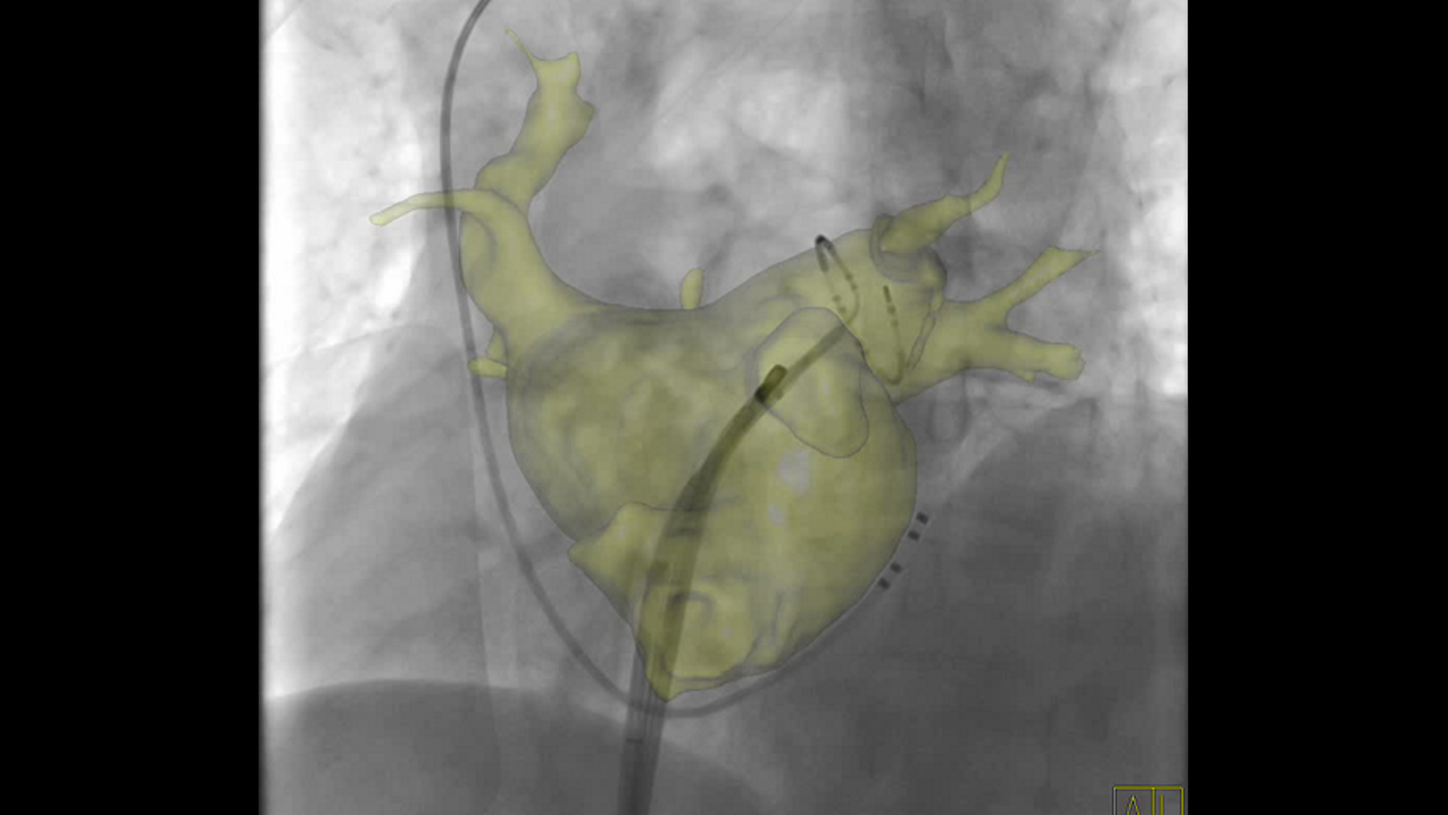

Simple and fast 3D imaging, everywhere

Generate 3D acquisitions with excellent spatial and soft tissue resolution whatever your clinical case is. With up to 95°/s rotation speed, ARTIS icono systems can acquire syngo DynaCT images in just 2.5 seconds with fewer motion artifacts and less use of contrast media.3 Simple and fast 3D imaging from head to toe with 200° rotation range gives you confidence in procedure planning.

Precise system movements

Precision is key to improve the workflow in complex procedures. The reuse of vessel maps for DSA and 3D Roadmap even after C-arm and table movements speeds up the intervention and reduces dose and use of contrast media. ARTIS icono supports this with a (re)positioning accuracy of better than 0.5 mm.